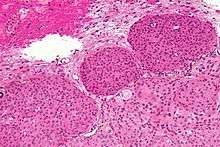

Micrograph of a meningioma showing the characteristic whorling, HPS stain

Micrograph of a meningioma with brain invasion (WHO Grade II); the tumour (bottom/right of image) has the typical "pushing border" invasion into the cerebral cortex (top/left of image), HPS stain

Histologically, meningioma cells are relatively uniform, with a tendency to encircle one another, forming whorls and psammoma bodies (laminated calcific concretions).[12] As such, they also have a tendency to calcify and are highly vascularized.